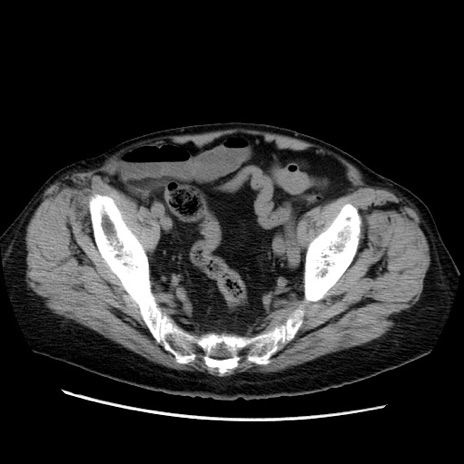

症例21(横断像)

【症例】70歳代男性

【主訴】腹痛

【現病歴】肝硬変・肝細胞癌にてかかりつけの方。約9時間前に食後より腹痛出現。症状が徐々に増悪し、嘔吐出現したため来院。

【既往歴】肝硬変、肝細胞癌(RFA、TACE後)

【身体所見】意識清明、表情苦悶様、BT 36℃、BP 129/78mmHg、P 88bpm、SpO2 97%(RA)、右上腹部から心窩部にかけて圧痛あり、反跳痛なし、筋性防御あり。

【データ】WBC 5800、CRP 0.16